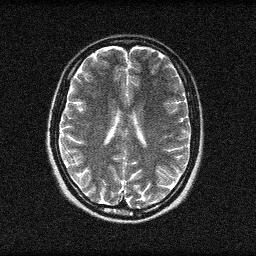

Reconstruction

Mean PSNR Across All Scenes

| scene_00 | 16.369188751529634 | 0.3769596313670564 | 28.91599361455386 | 0.8937325593738555 | 43.0888232643681 | 0.9970601105022431 |

| scene_01 | 17.02984109629589 | 0.5076141905187631 | 29.54697836453365 | 0.9088858192167282 | 44.00498178524224 | 0.9974331602373123 |

| scene_02 | 19.876634796830935 | 0.5132084125883123 | 29.296469693787934 | 0.8901788054246903 | 45.80916505985154 | 0.9983439806976319 |

| scene_03 | 16.209230008064964 | 0.3451008090497886 | 28.211197909256423 | 0.8836538261470794 | 42.81516446798818 | 0.997371546825409 |

| Mean | 17.371223663180356 | 0.4357207608809801 | 28.99265989553297 | 0.8941127525405883 | 43.929533644362515 | 0.9975521995656491 |